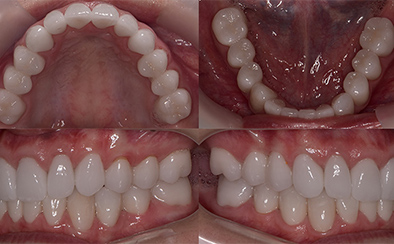

治療前

治療後

なるべく歯を残して、歯の神経も可能な限り保存し残していく方向で治療方法を検討しました。むし歯が大きく神経が侵されている歯は、抜髄を行い、精密根管治療の後にセラミックスクラウンを被せる治療方法を策定しました。患者さんのご希望と了解を得て治療を開始しました。

むし歯治療では、丁寧にむし歯だけを除去して健全な歯質だけを残します。名取歯科医院では、ラバーダムとマイクロスコープの使用が標準です。歯の根と神経の治療(根管治療)も行っていきます。

ラバーダムとはゴム製のシートで、治療する歯だけを露出させるように丁寧に切り取り、お口に装着します。唾液の中には天文学的な数の細菌が存在するため、一度治療した歯が再び悪化して再治療とならないためには、ラバーダムを装着し唾液や細菌に触れないように防湿を施した環境で治療することが何よりも大切で、歯科治療の基本です。歯の根元の黒い部分は膿の溜まった袋です。

むし歯が進行することで歯の神経まで細菌に侵されてしまった場合、昭和型の歯科治療では歯を抜いてしまう抜歯が当たり前でした。しかし、歯を抜いてしまうことで歯並びの乱れなど、ほかの歯への大きな影響があります。そこで自分の歯をできるだけ残すことを考えた「根管治療」や「保存治療」が選択されるようになってきました。

治療後の写真です。きちんと歯の根の治療(根管治療)を施すことで膿の袋も消失します。

歯ぐき(歯肉)の治療も大切です。歯ぐきを健康的な状態に治療していくことで、お口全体を審美的に優れた美しい状態に改善できます。このように歯ぐき(歯肉)の治療を行うことで、炎症を抑え、健康な状態をつくることができます。歯ぐきのコンディションを回復させると同時に、仮歯を入れます。しかしこれは治療中の隙間を埋めたり見た目を取り繕う「仮歯」とは異なります。プロビジョナルレストレーションと言い、最終的な歯(本歯)と同じ形体をもつ歯で、治療した歯や周囲の歯、反対側の歯、歯ぐきなどお口全体の回復と調和を整える大切な治療プロセスです。もちろんこの期間に仮歯での噛み合わせ、咀嚼や嚥下、または発音や発語など機能的な回復に不具合がないか、顎関節への影響や負担がないか検証する期間でもあります。

仮歯で機能回復の確認を行い、そしてさらに微調整を行います。機能的・審美的に改善を確認できた仮歯の形態を元にセラミックスクラウンを作製します。熟練した歯科技工士によるセラミックス制作を行い、装着後に最終的な微調整(咬合調整)を施し、むし歯治療、歯の根の神経治療(根管治療)、白いセラミックスによる修復治療のすべてが終了しました。

| 費用 | ジルコニアセラミック24本:5,280,000円 根管治療(小臼歯5本):770,000円 根管治療(前歯6本):792,000円 合計:6,842,000円 |